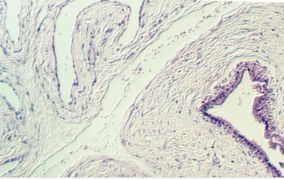

At about day 15, the trophoblast shell sends villi deeper into the endometrium. These villi are filled with mesenchyme (called secondary villi) and will, by the end of the 3rd week, contain blood vessels (tertiary villi.) Maternal blood percolates slowly in the space created outside the villus. Look at slide 89 in your class slide set. The right hand section shows a young placenta. Look at the section with the low power. In the lower left of the section, there is a twisted, folded and otherwise distorted portion of the chorionic plate. It is amass of connective tissue covered by two types of epithelia. The side lined by flat epithelium is continuous with the amniotic sac. It faces the embryo. The side lined by two layers of trophoblast cells faces the uterus and gives rise to the villi. The photos below show the chorionic plate and related structures. The first photo shows the side facing the uterus.

The following photos show the portion facing the embryo. It is distinguished by the simple squamous epithelium. In the lower right corner, one can see the denser epithelium of the side facing the uterus.